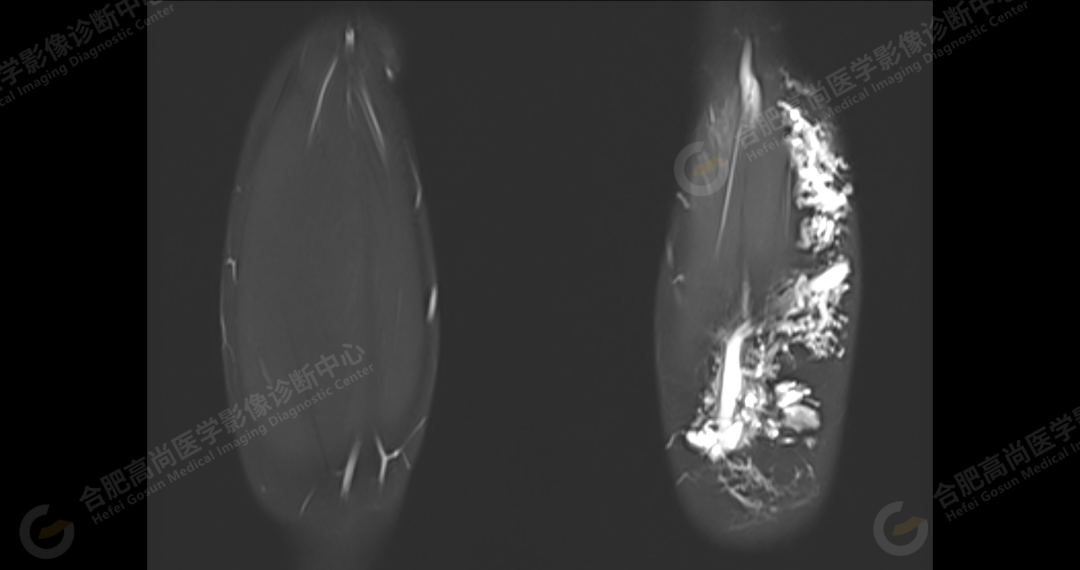

左侧髂骨内侧及闭孔内肌前方可见网格状异常信号影,边界欠清,T1WI 呈低信号,T2 压脂呈高信号,病变连续,延伸至臀肌内;左侧臀肌间隙及皮下、左大腿后部肌肉群及皮下、左膝前外侧及腘窝皮下、左小腿后侧皮下累及比目鱼肌及内外侧腓肠肌、左内外踝皮下、左足背足底及左足肌间隙内可见大片状、结节状弥漫性异常信号影,形态不规则,分布不均匀,边界不清,T1WI 呈低信号,T2WI 压脂后病灶呈高信号,部分病灶内可见网格状低信号,左足部肌间隙增宽,第 2-4 跖骨稍受压,骨质结构完整。左髋关节、膝、左踝关节间隙正常,无明显狭窄及增宽,关节面光滑,关节腔内无积液,左股骨、胫腓骨及踝部各组成骨骨质结构完整,未见明显异常改变。

左侧盆腔及下肢皮下及部分肌间隙内漫状血管瘤,请结合临床。